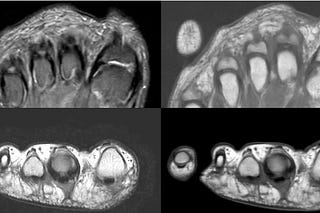

COD 145 - A Swollen Face and The Tincture of Time

3 months old in Jul 2023 with diffuse facial swelling due to mandibular periosteal reaction and masseter edema